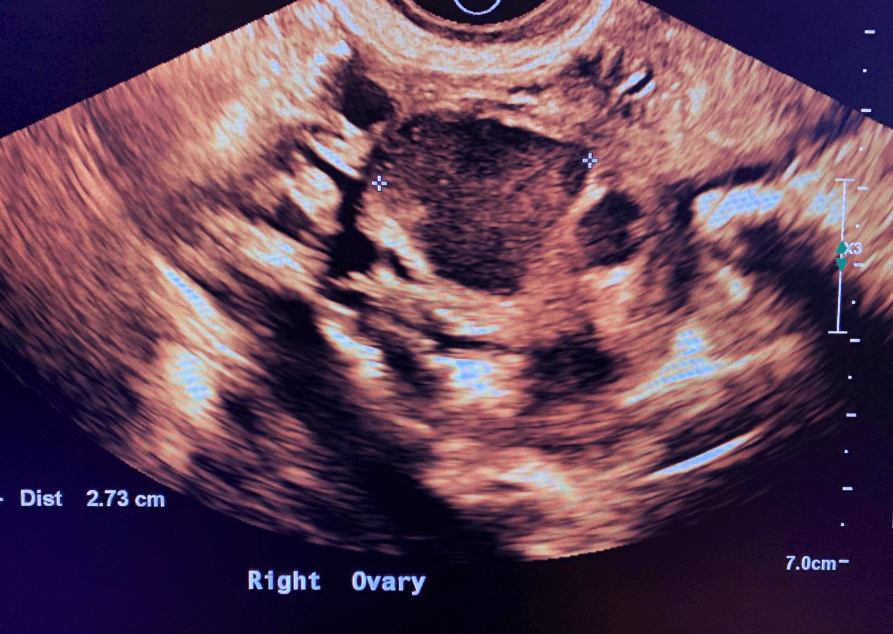

Endometrioma on the ovary

- Endometriomas on the ovaries